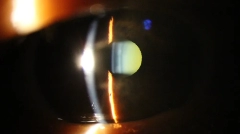

Catarata

Cirurgias